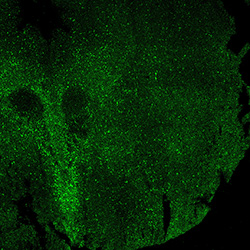

11PCW

MAP2

11PCW human midbrain